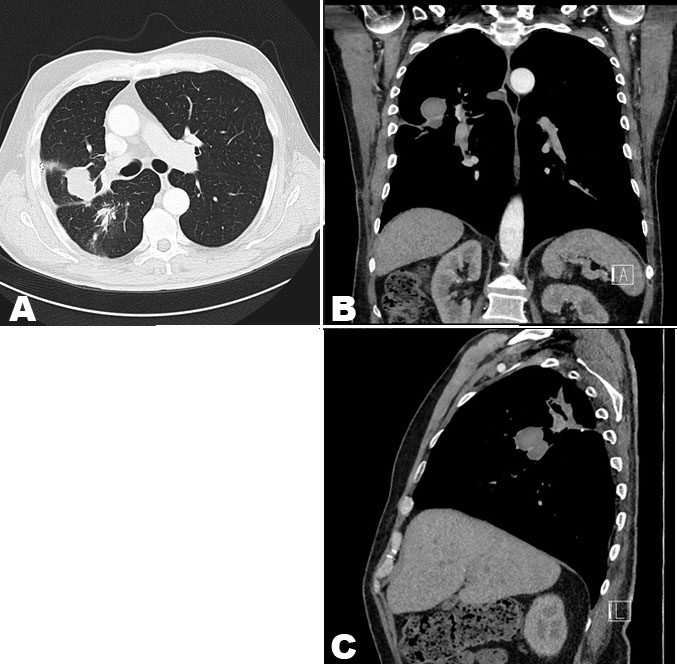

Due to concerns for malignancy, imaging investigations were performed. The chest X-ray (CXR) revealed a patchy pulmonary consolidation in the basal aspect of the right upper lobe with pleural thickening at the right lung base (Figure 1). The chest CT scan showed a 45 × 25 mm spiculated lesion in the posterior segment of the right upper lobe and no associated lymphadenopathy (Figure 2). He then underwent two CT-guided core biopsy in his right upper lobe, which yielded negative for malignant cells on cytology but revealed chronic organizing inflammation with stromal fibrosis and granulation tissue suggesting an infective or inflammatory process. The histological analysis was negative for acid-fast bacilli or fungal elements.

Figure 2: CT. (A) Transverse, (B) Coronal, and (C) Sagittal view of CT scan revealing a 45 × 25 mm spiculated lesion in posterior segment of the right upper lobe with no associated axillary or mediastinal lymphadenopathy. There is no consolidation or air bronchograms.